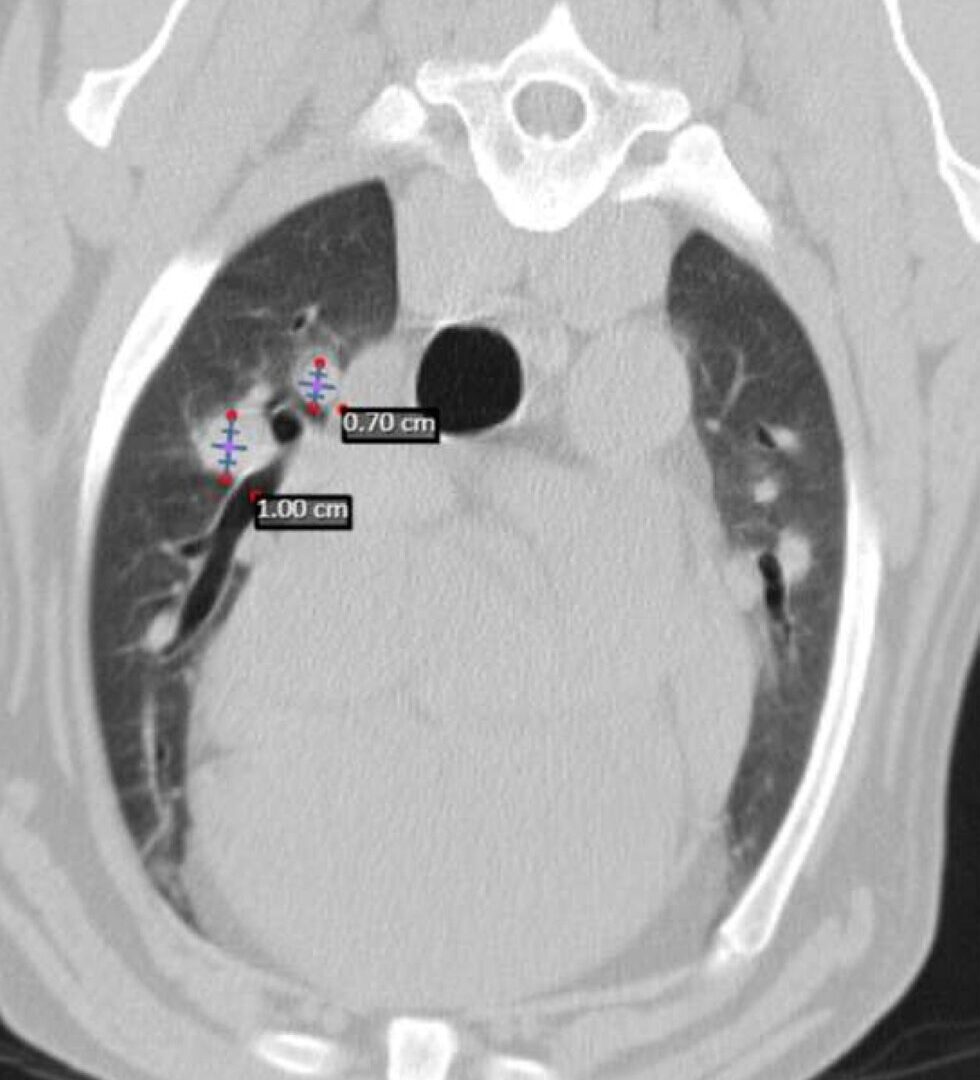

Dos semanas más tarde se realiza el TC de reestadiaje y se detecta la presencia de enfermedad metastásica en pulmón. Adicionalmente, la afectación completa del paladar y la invasión en cavidad nasal hacen que se descarte la cirugía como terapia local.

En el momento del estadiaje inicial, el paciente presenta un buen estado general, pero se evidencia el crecimiento de la lesión primaria y la existencia de metástasis regionales y a distancia según TC. Se administra la segunda dosis de la vacuna de melanoma y se planifica radioterapia paliativa, seguida de quimioterapia adyuvante con carboplatino. Cuatro semanas más tarde se completa la radioterapia paliativa en cinco sesiones (22.5Gy) dirigida al melanoma oral y metástasis en ganglios linfáticos mandibulares y retrofaríngeos bilaterales. Los cuidadores rechazan finalmente el tratamiento con carboplatino adyuvante.

A los 18 meses del diagnóstico, los cuidadores refieren la aparición de hifema y exoftalmia en el ojo derecho, lo que sugiere metástasis, además de una masa perianal compatible con neoplasia indiferenciada (posible melanoma amelanótico). En el estudio de TC se documenta una respuesta completa de la lesión primaria y metástasis nodales y una remisión casi completa de las metástasis pulmonares (lesiones milimétricas equívocas) (imagen 1). Se realiza la resección de la masa perianal, pero los cuidadores rechazan la enucleación.

A los 28 meses se realiza un TC de re-estadiaje antes de considerar el segundo protocolo de radioterapia, donde se documenta una progresión objetiva de la masa oral y ligera progresión de la metástasis pulmonar (imagen 1).